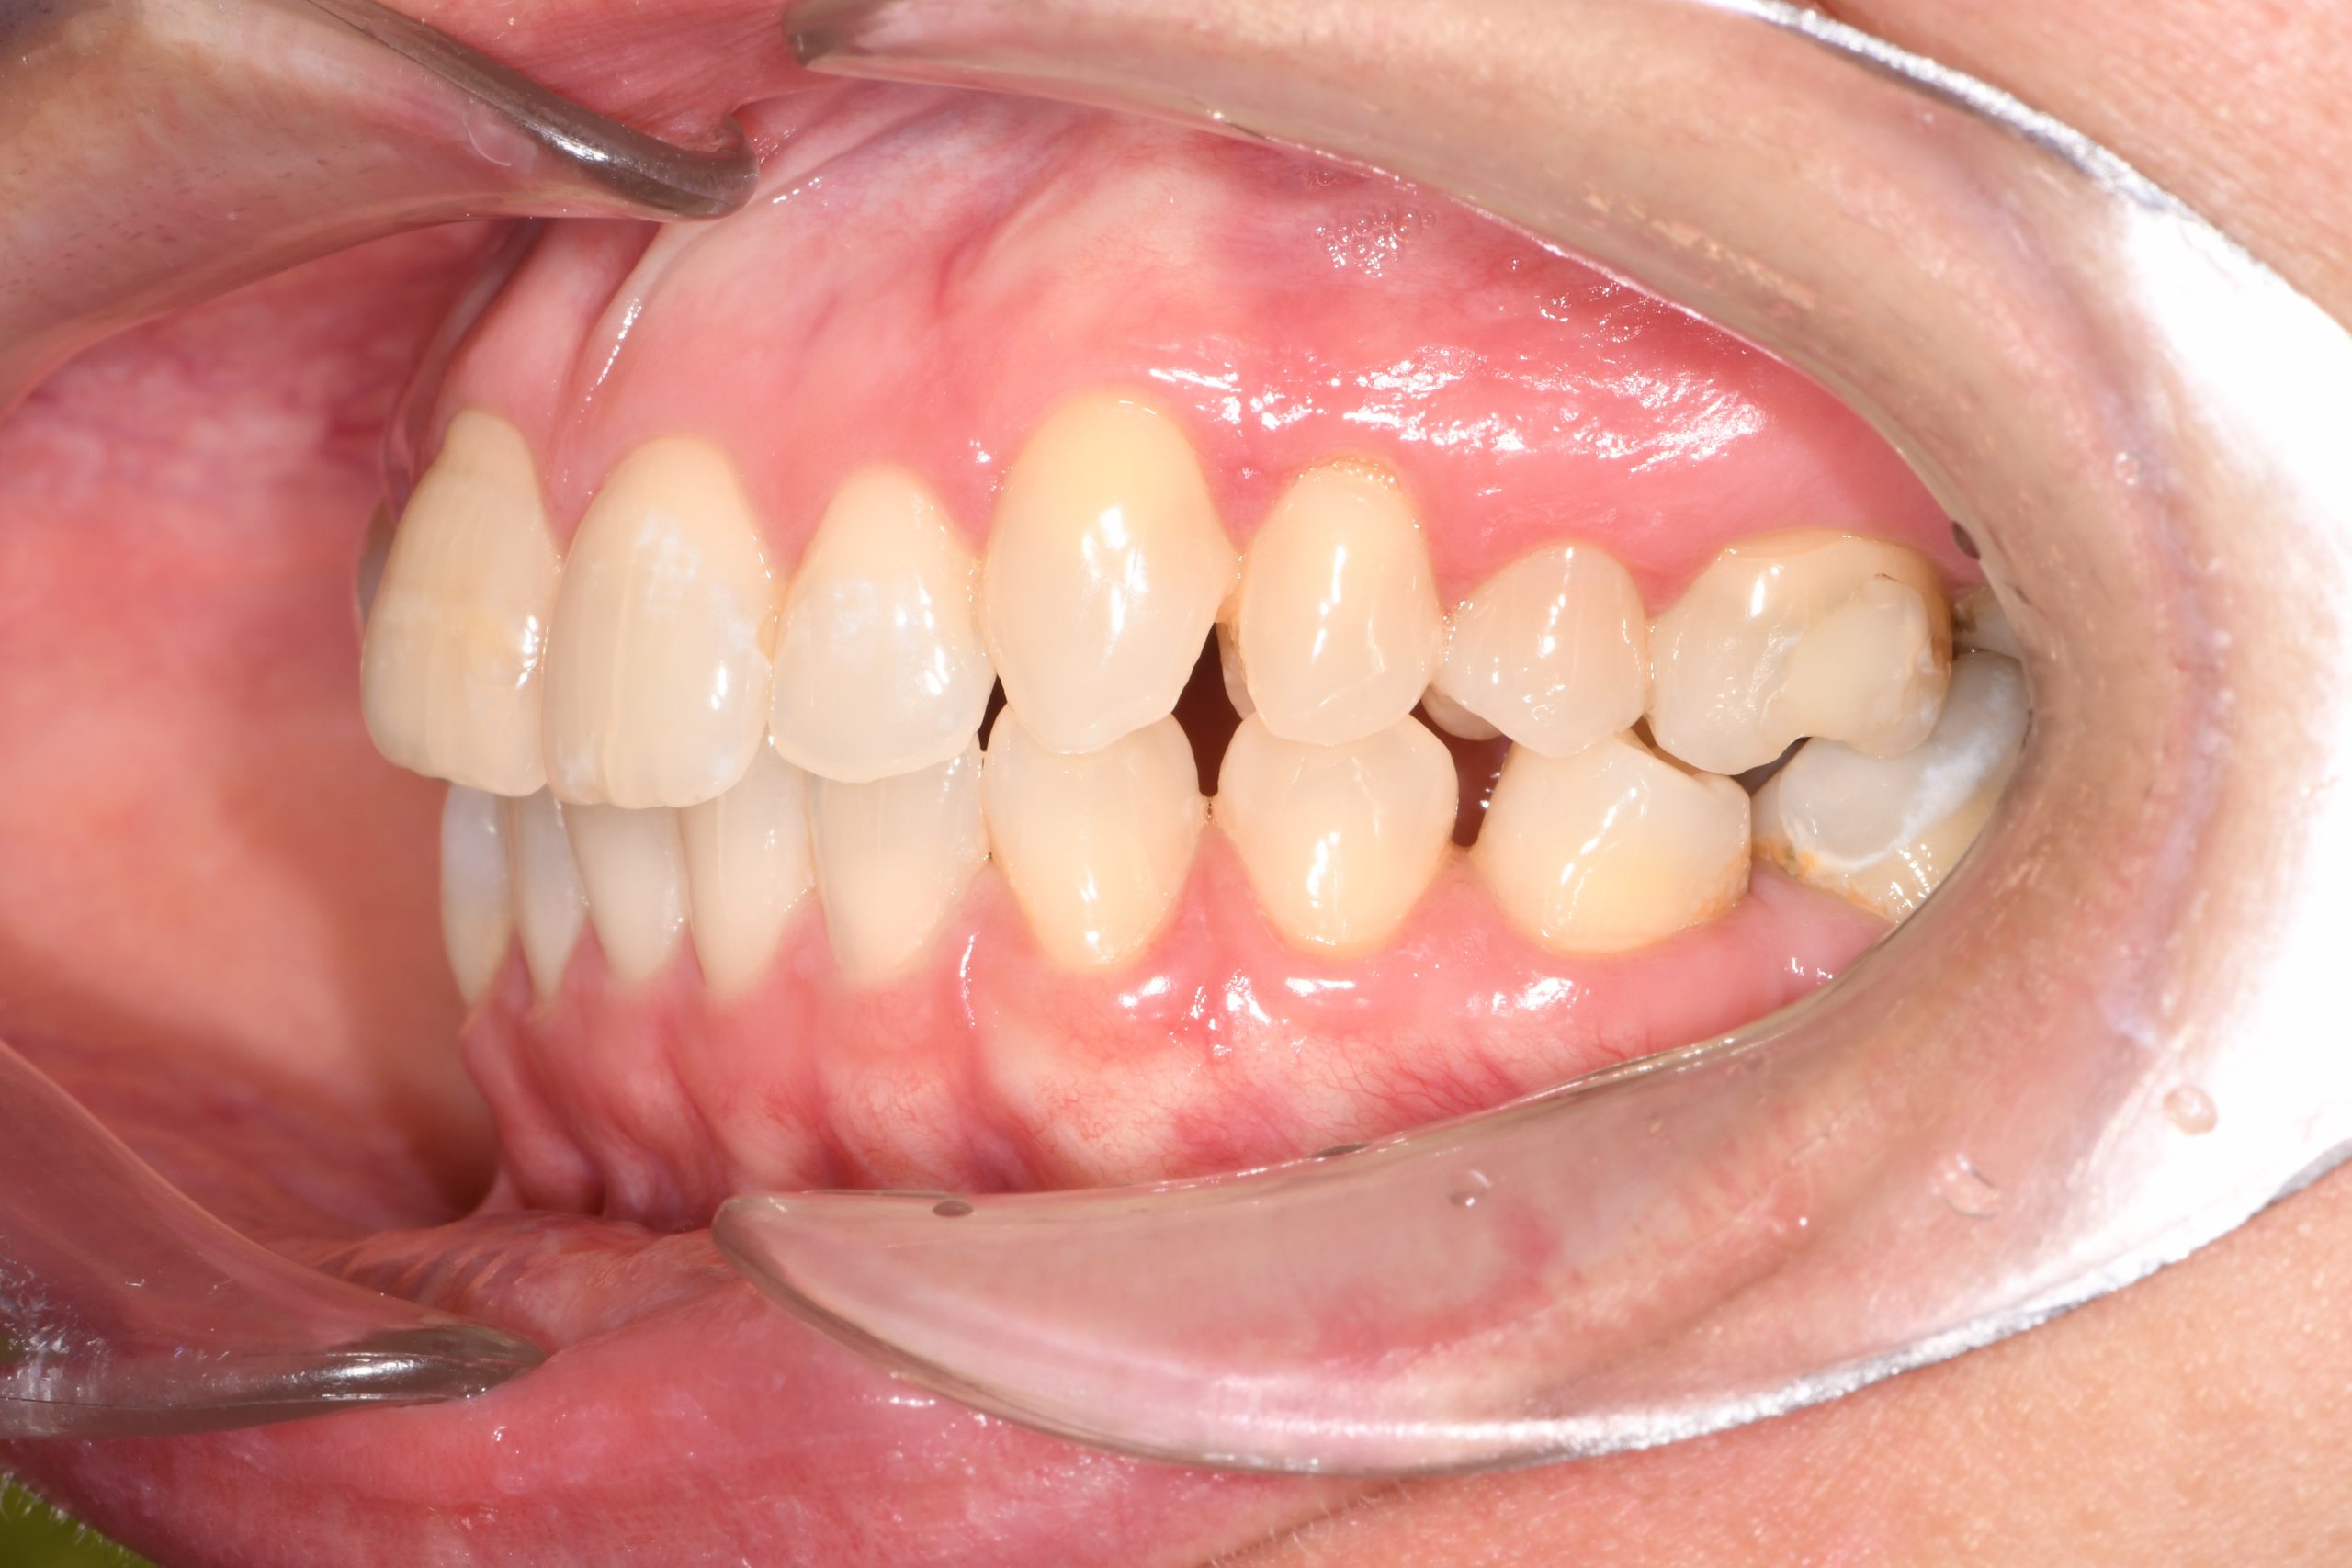

Az elmúlt évekből rengeteg szakmai referenciát tudnánk bemutatni, amelyek különböző fogszabályozási problémákat oldottak meg. Válogatva a több száz esetből, ezen az oldalon olyan képeket, információkat igyekeztünk bemutatni, amelyeknek a segítségével a jövőbeni pácienseinknek azt tudjuk üzenni: A Te fogsorod is lehet gyönyörű!

(Képeket a Pácienseink külön írásos beleegyezésével mutatjuk be!)